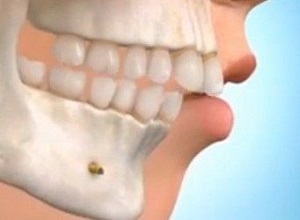

Ortodonti, Dişlerinizdeki ve Çenenizdeki Düzensizlikleri DüzeltirOrtodonti Tedavisi

Ortodonti, Dişlerinizdeki ve Çenenizdeki Düzensizlikleri DüzeltirOrtodonti Tedavisi -